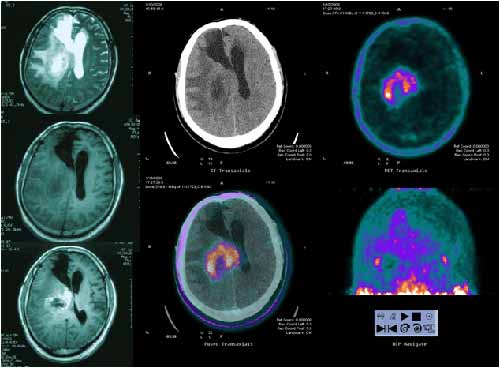

pet显像为放疗定位提供生物靶区 男性,51,胶质瘤术后3年,近期明显头痛,呕吐mri考虑局部复发; 11c-cho病变显著摄取增高,符合复发表现,复发区域大于m

图解petct